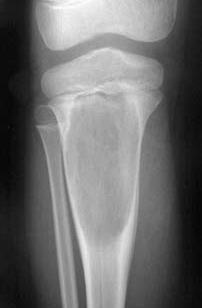

56. A csontok daganatos megbetegedései

A csonttumorok éjszaka fokozódó, állandó fájdalmat idéznek elő.

Patológiás törés gyakran előfordulhat.

A diagnózis gyanuját az általános klinikai tünetek, a gyorsult süllyedés, valamint a radiológiai elváltozások alapozzák meg.